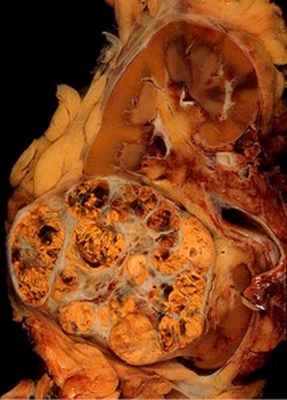

Макроскопическое описание

Почка с паранефральной клетчаткой и опухолевым конгломератом из области ворот, размером 22×14×5,5 см. Паренхима нижней половины почки замещена разросшейся опухолевой тканью, диаметром 5 см, преимущественно белесого цвета с четкими границами, дольчатого вида, с кровоизлияниями и очагами некроза.